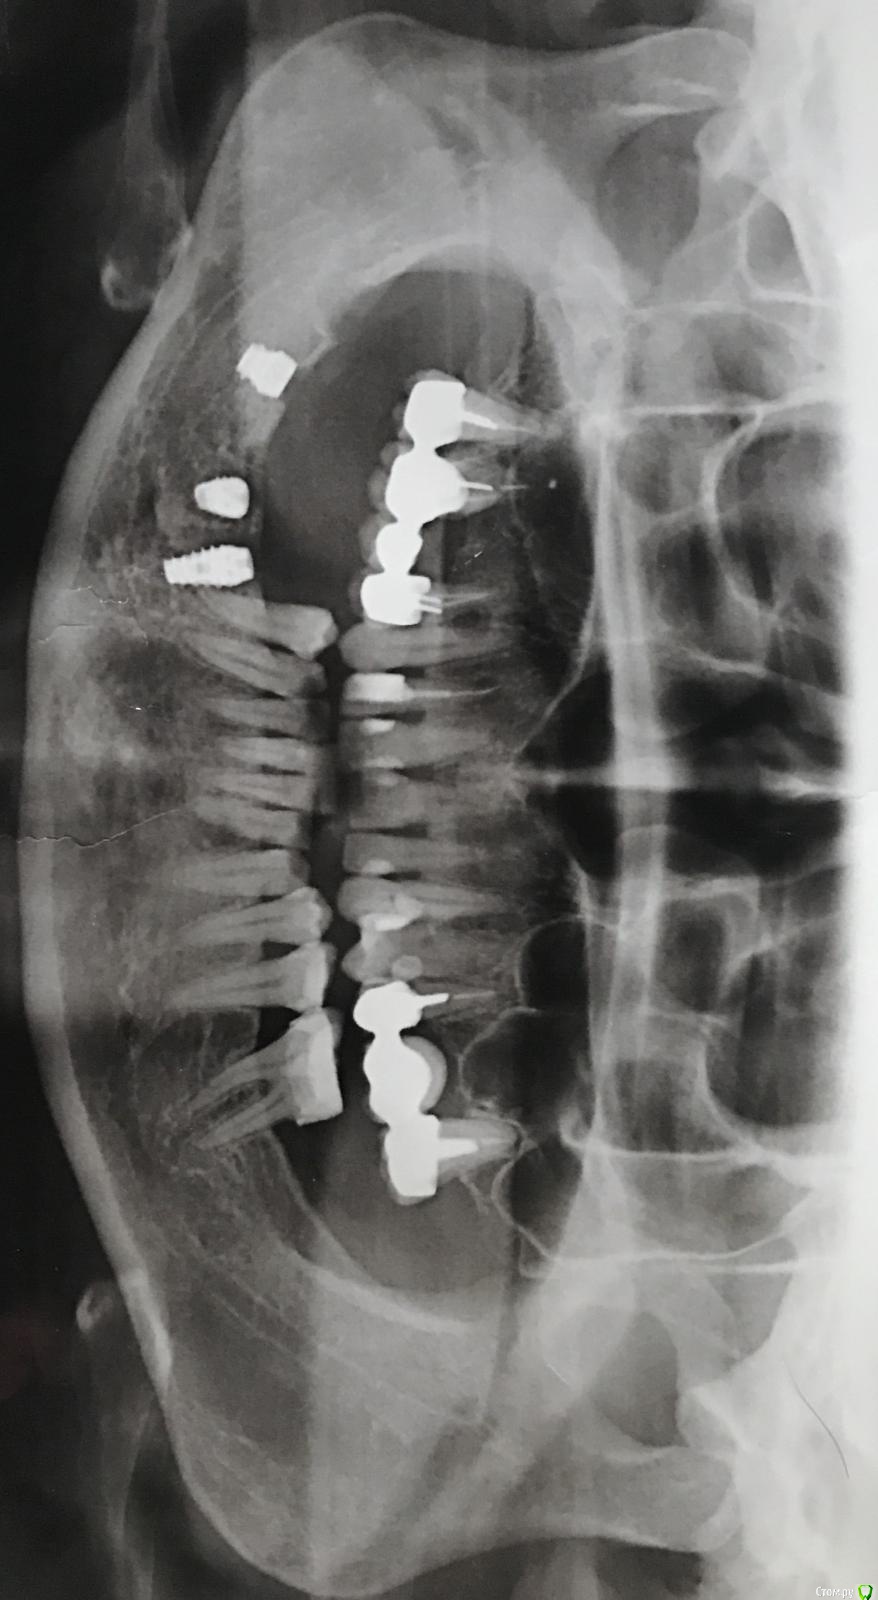

1979ната Опубликовано 3 февраля, 2017 Поделиться Опубликовано 3 февраля, 2017 (изменено) После имплантации прошло две недели, боль не совсем прошла. Болят три зуба возле импланта - боль ноющая. При постукивании по зубу врачом - острая. Врач предлагает депульпировать нерв. Посмотрите - действительно это необходимо. Изменено 3 февраля, 2017 пользователем 1979ната Ссылка на комментарий

dok1 Опубликовано 3 февраля, 2017 Поделиться Опубликовано 3 февраля, 2017 По снимку похоже на контакт импланта с корнем. И, возможно, с нижнечелюстным нервом. Нужно сделать томограмму и выложить срезы этой области. Но вероятность причины в контакте корня и импланта достаточно большая. Ссылка на комментарий

dok1 Опубликовано 4 февраля, 2017 Поделиться Опубликовано 4 февраля, 2017 Другие можно было подлиннее попробовать поставить. Но истинную картину покажут только срезы КТ. Ссылка на комментарий